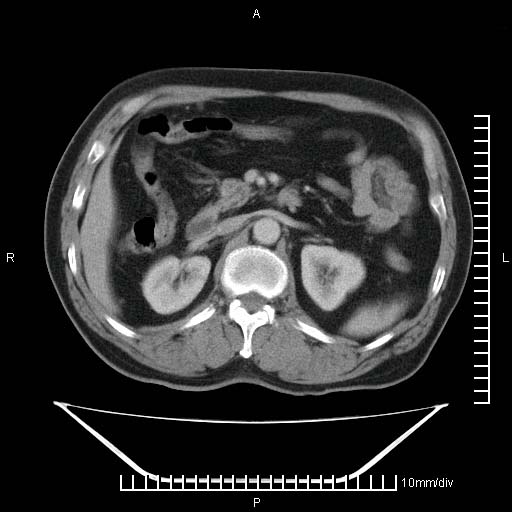

标题: CT25082:肝脏增强:男性,70岁 [打印本页]

标题: CT25082:肝脏增强:男性,70岁

患者以心脏疾病收住院,腹部无明显症状,b超查肝脏有占位。

牛眼征,中心坏死无强化,外缘强化,最外缘又见低密度,考虑转移,与脓肿鉴别

肝内多发转移瘤,右下肺炎症并少量胸水。胃壁增厚建议胃镜,胰尾部“病变”为肠管。

1)肝脏多发性转移瘤(不排除胰尾癌转移所致可能)。2)腹水。3)右侧少量胸腔积液。

ct25082 结果:转移瘤

外院mr结果:胰尾恶性占位。

肝多发低密度灶;轻度强化,较水密度高,考虑转移,不排除肝脓肿